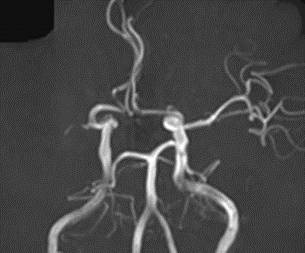

閉塞した脳血管